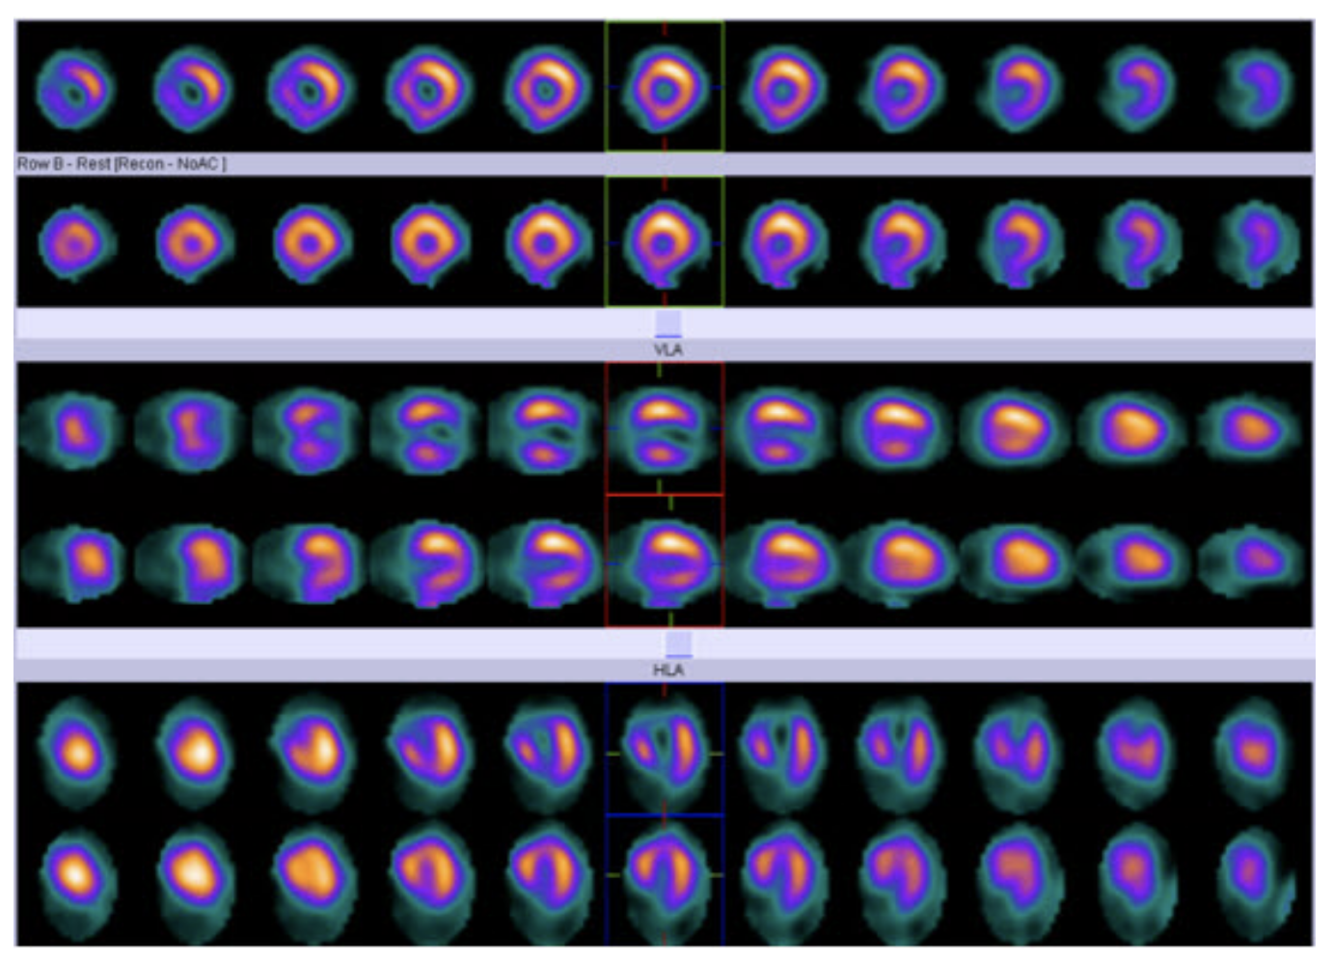

Describe the findings:

uniform breast attenuation